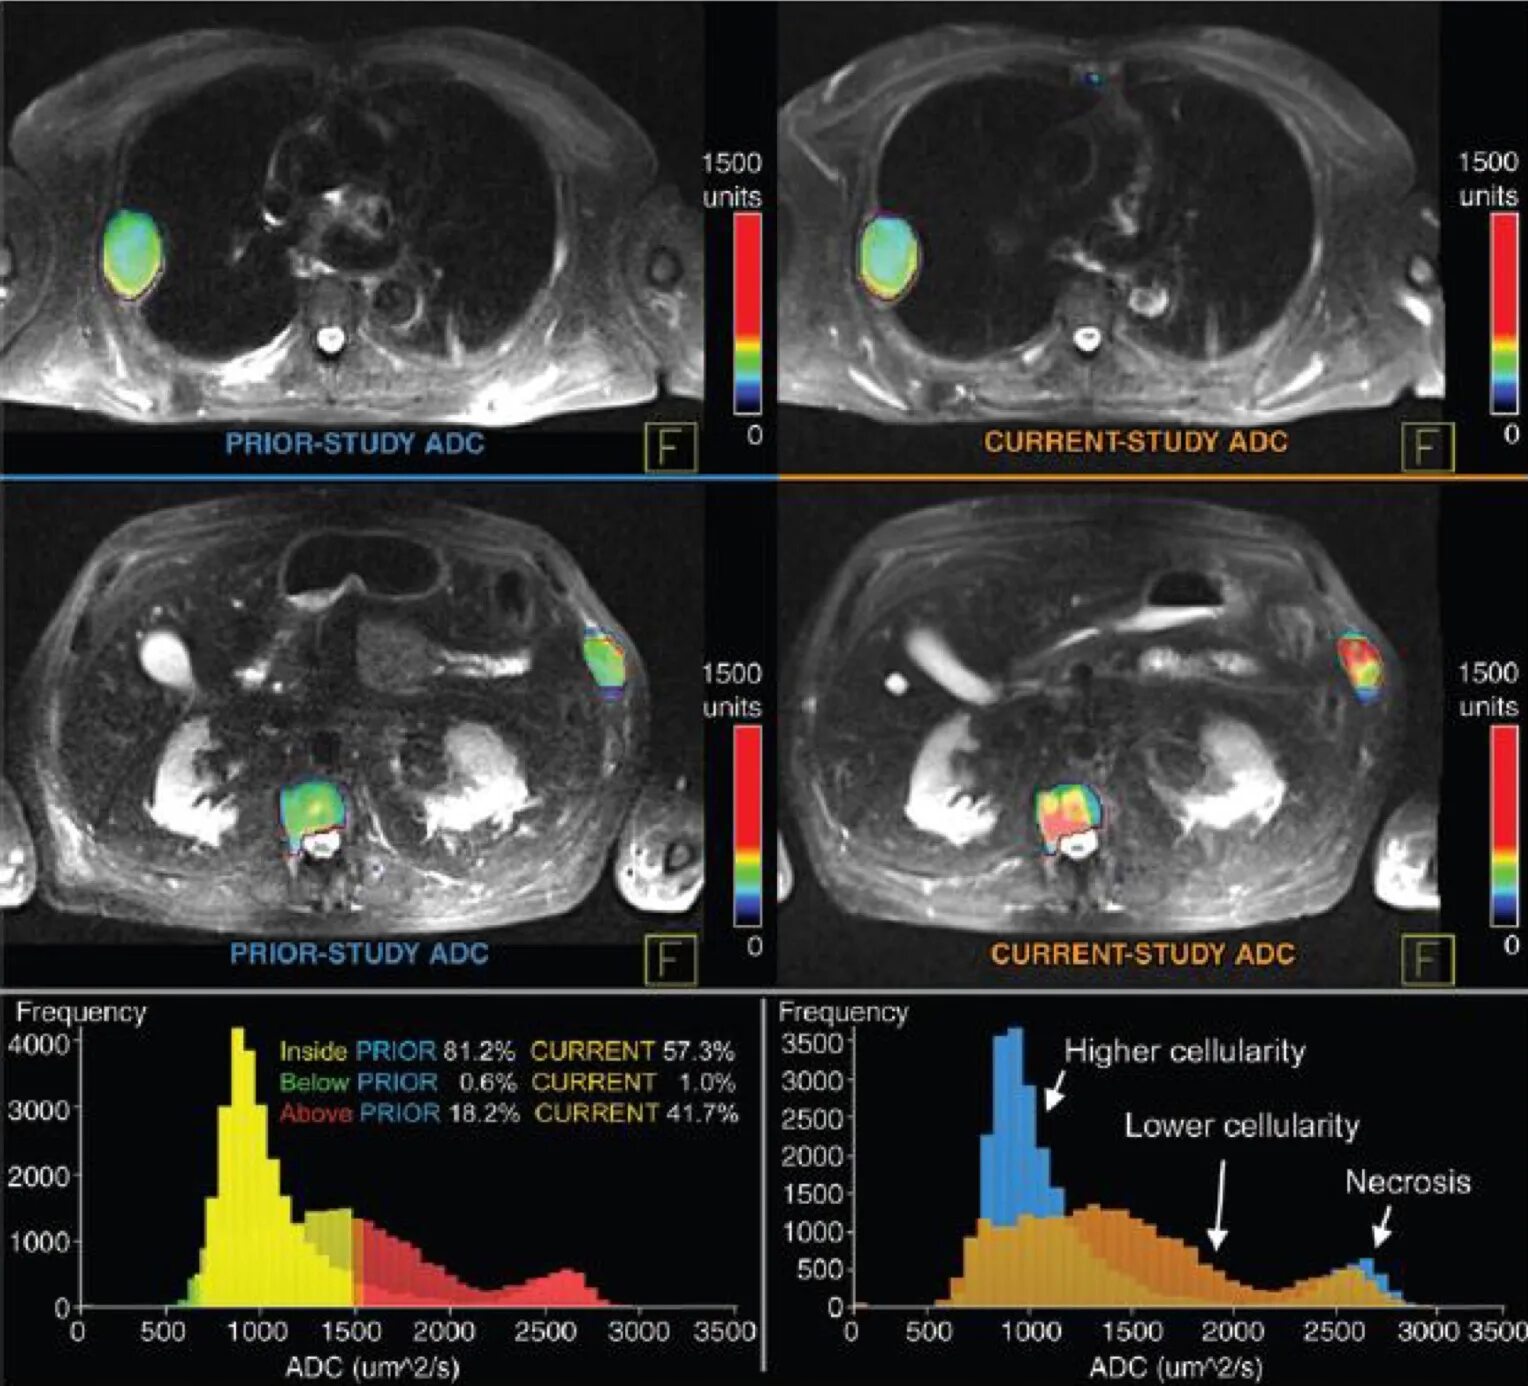

Без ограничение диффузии